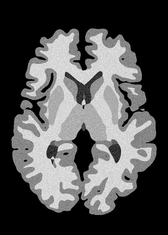

4.2 Registration to a 100 micron ex-vivo brain MRI volume

To showcase the efficacy of our method on real large scale images, we register a 250 in-vivo MRI image (Lüsebrink et al., 2017) to a 100 ex-vivo FLASH human brain volume (Edlow et al., 2019). This represents an inverse problem with more than 11.2B optimizable parameters (compared to 20M for clinical datasets), or 44.8GB of GPU memory. The entire problem does not fit on most GPUs, necessitating distributed multimodal registration. We optimize a composite transform - affine followed by a diffeomorphic mapping; details can be found in Section E.1. Multimodal deformable registration took 58 seconds on 8 NVIDIA A6000 GPUs, which is unprecedented at this resolution. Fig. 6 shows qualitative results, highlighting the ability to register highly detailed structures such as cerebellar white matter; these structures are not visible at macroscopic scales. The resultant advantages of performing registration at this scale can allow researchers to characterize the neuroanatomy at microscopic resolutions and allow morphometric analysis of cortical layers and subcortical nuclei among other structures.